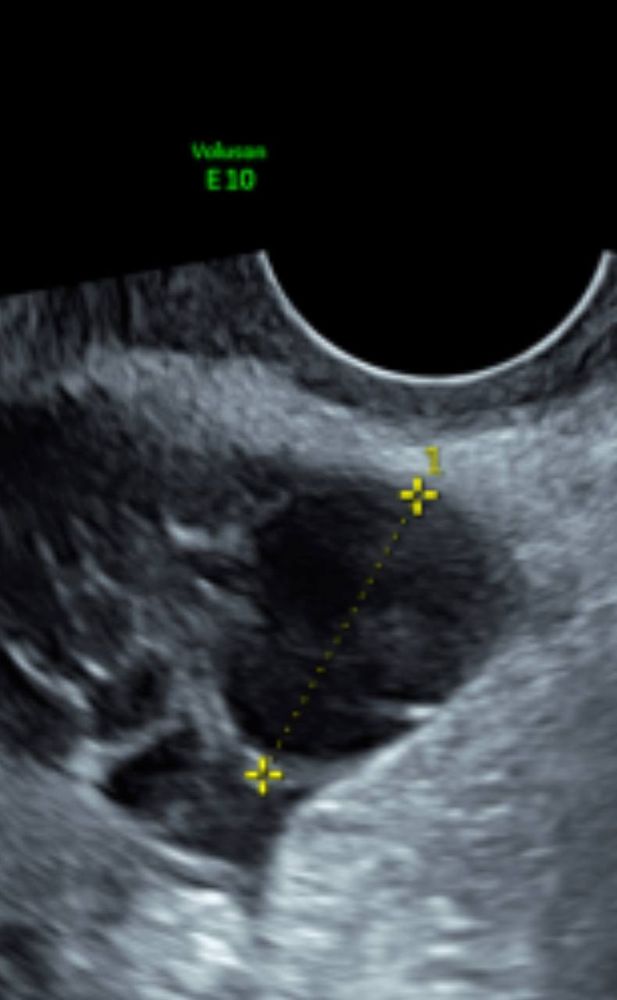

Добрый день, такой вопрос может у кого-то было такое, 14 дней назад сделала Лапароскопию (делали насечки) в связи с бесплодие, сегодня 14 день цикла, ждала овуляцию, но она как мне сегодня сказали была 3 дня назад, что вот жёлтое тело 2.5 на 2.2 см, на фото выше, что увы и ах прозивали, дак я вот теперь и думаю может ЖТ перепутали с ДФ, как-то рано она пришла, врач УЗИ сказала что это точно ЖТ так как кровоток есть ( на фото с лева 2 белые точки)

Вообще сколько видела жёлтое тело на узи своих, то оно имеет неровные края, типо звёздчатое, а у Вас ровный круг,что больше на фолликул похоже.

Elenochka (Дважды мама в 2021), да вот я тоже читала, что при ЖТ не ровные края, а тут прям ровный круг

Они совершенно по разному на узи. У жт хорошо видно кровоток. Его смотрят как-то разноцветно, хорошо видно. И показывают. А еще жидкость в брюшной полости должна быть. ДФ это полностью черный круг без кровотока (жидкость поглощает уф лучи и выглядит черным цветом)

Больше похоже на доминантный фолликул